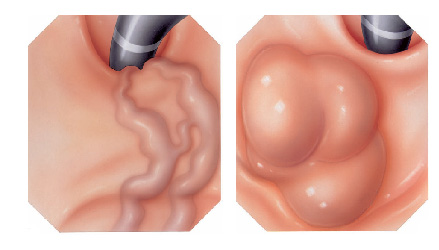

Mucosectomia é o procedimento realizado quando há necessidade de retirada de lesões maiores do trato gastrointestinal.

O exame de Mucosectomia é realizado através de injeção de liquido embaixo da lesão, através de uma agulha específica. Com isso a lesão se destaca das camadas mais profundas do intestino, diminuindo o risco de perfuração.

A retirada da lesão é feita com uma alça de polipectomia e o material é encaminhado para estudo anatomopatológico (no microscópio) da mesma forma que ocorre nas biópsias.

O que são pólipos?

Pólipos são crescimentos na parede interna do tubo digestivo em órgãos como o esôfago, estômago, duodeno e cólon. O cólon e o reto são partes do intestino grosso.

Por que devem ser removidos?

Se não forem removidos cedo, alguns pólipos podem se tornar cancerosos. Se pólipos cancerosos não são tratados, eles são uma ameaça à vida. Porém mesmo sendo canceroso, se for ressecado precocemente e se este não estiver muito infiltrado, a simples retirada do pólipo pode resolver o problema.

Por que apenas a biópsia de um pólipo não é suficiente?

Geralmente apenas uma região do pólipo é que se apresenta de forma cancerosa. Se for realizada uma simples biópsia do pólipo, a região cancerosa pode não ser atingida e o diagnóstico de câncer não ser realizado. Para se ter certeza do diagnóstico, o pólipo inteiro deve ser removido através do procedimento chamado de polipectomia.

O que é a polipectomia?

A polipectomia é a remoção completa de um pólipo permitindo assim o diagnóstico exato e muitas vezes a cura do próprio problema. Existem várias técnicas para a realização do procedimento que dependem do tamanho e do tipo de pólipo a ser ressecado.

Polipectomia com pinça

Pequenos pólipos podem ser removidos com segurança usando-se apenas uma pinça.

Polipectomia com alça diatérmica

Pólipos maiores necessitam ser removidos com alça e corrente de cauterização. Este procedimento permite cortar a base do pólipo e ao mesmo tempo coagular o local para evitar sangramentos.

Porém alguns pólipos possuem a base (pedículo) largo onde passam vasos calibrosos e por isto tem risco aumentado de sangramento na retirada mesmo usando a corrente de coagulação.

Alguns pólipos não possuem a base alongada (pedículo), estes são chamados de pólipos sésseis. A remoção destes pólipos possui risco maior de perfuração do órgão pois como são planos ficam muito próximos da parede externa do órgão.

Mucosectomia

Para diminuir este risco, injeta-se com um uma agulha uma solução abaixo do pólipo para que ele levante e fique mais longe da parede do órgão. Após isto passa-se a alça diatérmica e realiza-se o

procedimento de polipectomia.